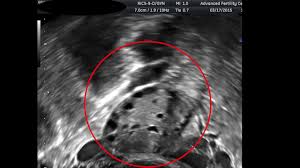

Antral Follicle Counts In Real Time Youtube